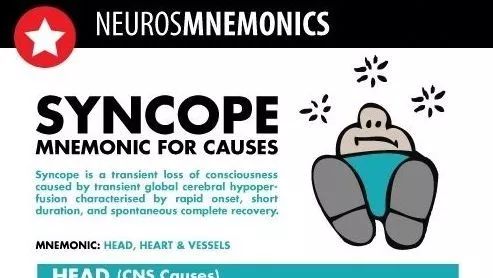

除了聊天答题跳一跳,你最该学会的是用微信涨知识! 医学界影像诊断与介入频道 · 公众号 · 医学 · 7 年前 · |